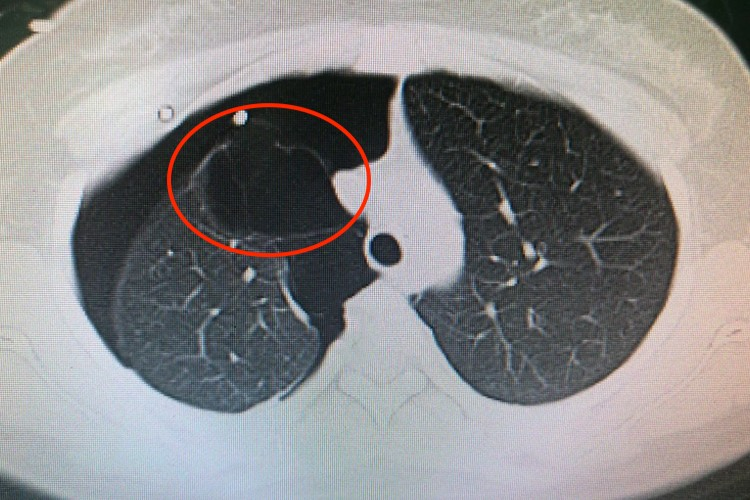

肺大泡是指肺大疱,其治疗方法因患者的具体情况而异,主要包括一般治疗、药物治疗、手术治疗等,并不存在绝对的最佳治疗方法。

- 肺大疱切除术:对于体积较大、占据一侧胸腔70%以上、影响肺功能或有自发性气胸等并发症的肺大疱,应考虑手术治疗。手术方法包括传统的开胸手术和微创的胸腔镜手术。胸腔镜手术具有创伤小、恢复快等优点,已成为首选的治疗方法。